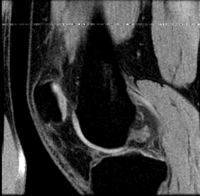

this is the fixed reference image. All images are aligned into this space lleft this is the moving image. The transform is calculated by matching this to the reference image LEGEND

lleft this indicates the reference image that is fixed and does not move. All other images are aligned into this space and resolution

lleft T1 SPGR lleft T1 SPGR

0.9375 x 0.9375 x 1.4 mm

256 x 256 x 112

RAS

• Button red fixed white.jpgreference/fixed : T1 SPGR , 0.9375 x 0.9375 x 1.4 mm voxel size, axial, RAS orientation.